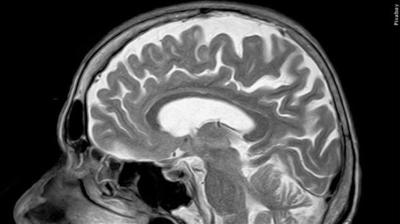

Both Kisunla and the Japanese drug, Leqembi, are laboratory-made antibodies, administered by IV, that target one contributor to Alzheimer's — sticky amyloid plaque buildup in the brain. Questions remain about which patients should get the drugs and how long they might benefit.